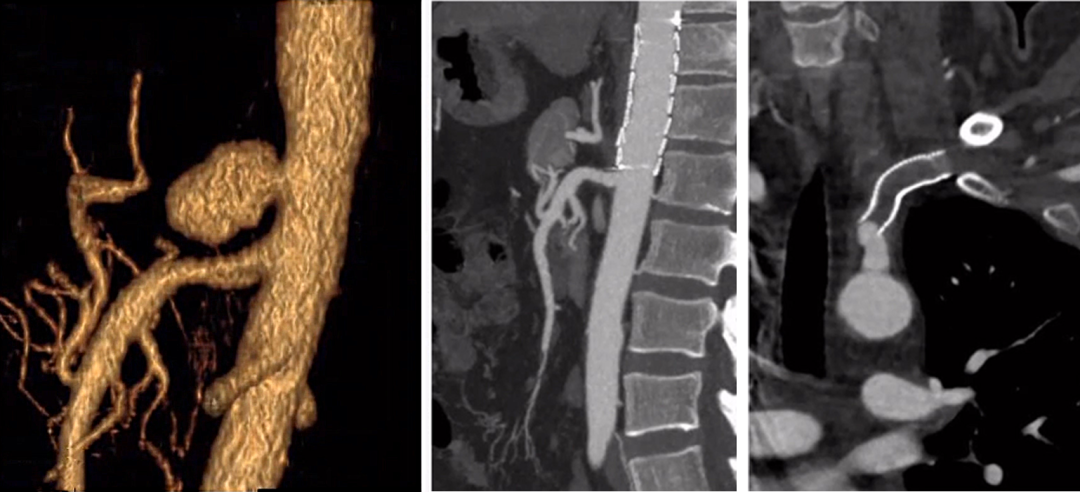

CTA:右肾动脉起始部假性动脉瘤形成(直径约1.5cm);肾下腹主动脉假性动脉瘤形成(直径约2cm)

双侧股动脉入路,右侧预置Perclose Proglide(支架入路),左侧6F 55cm长鞘,造影定位;